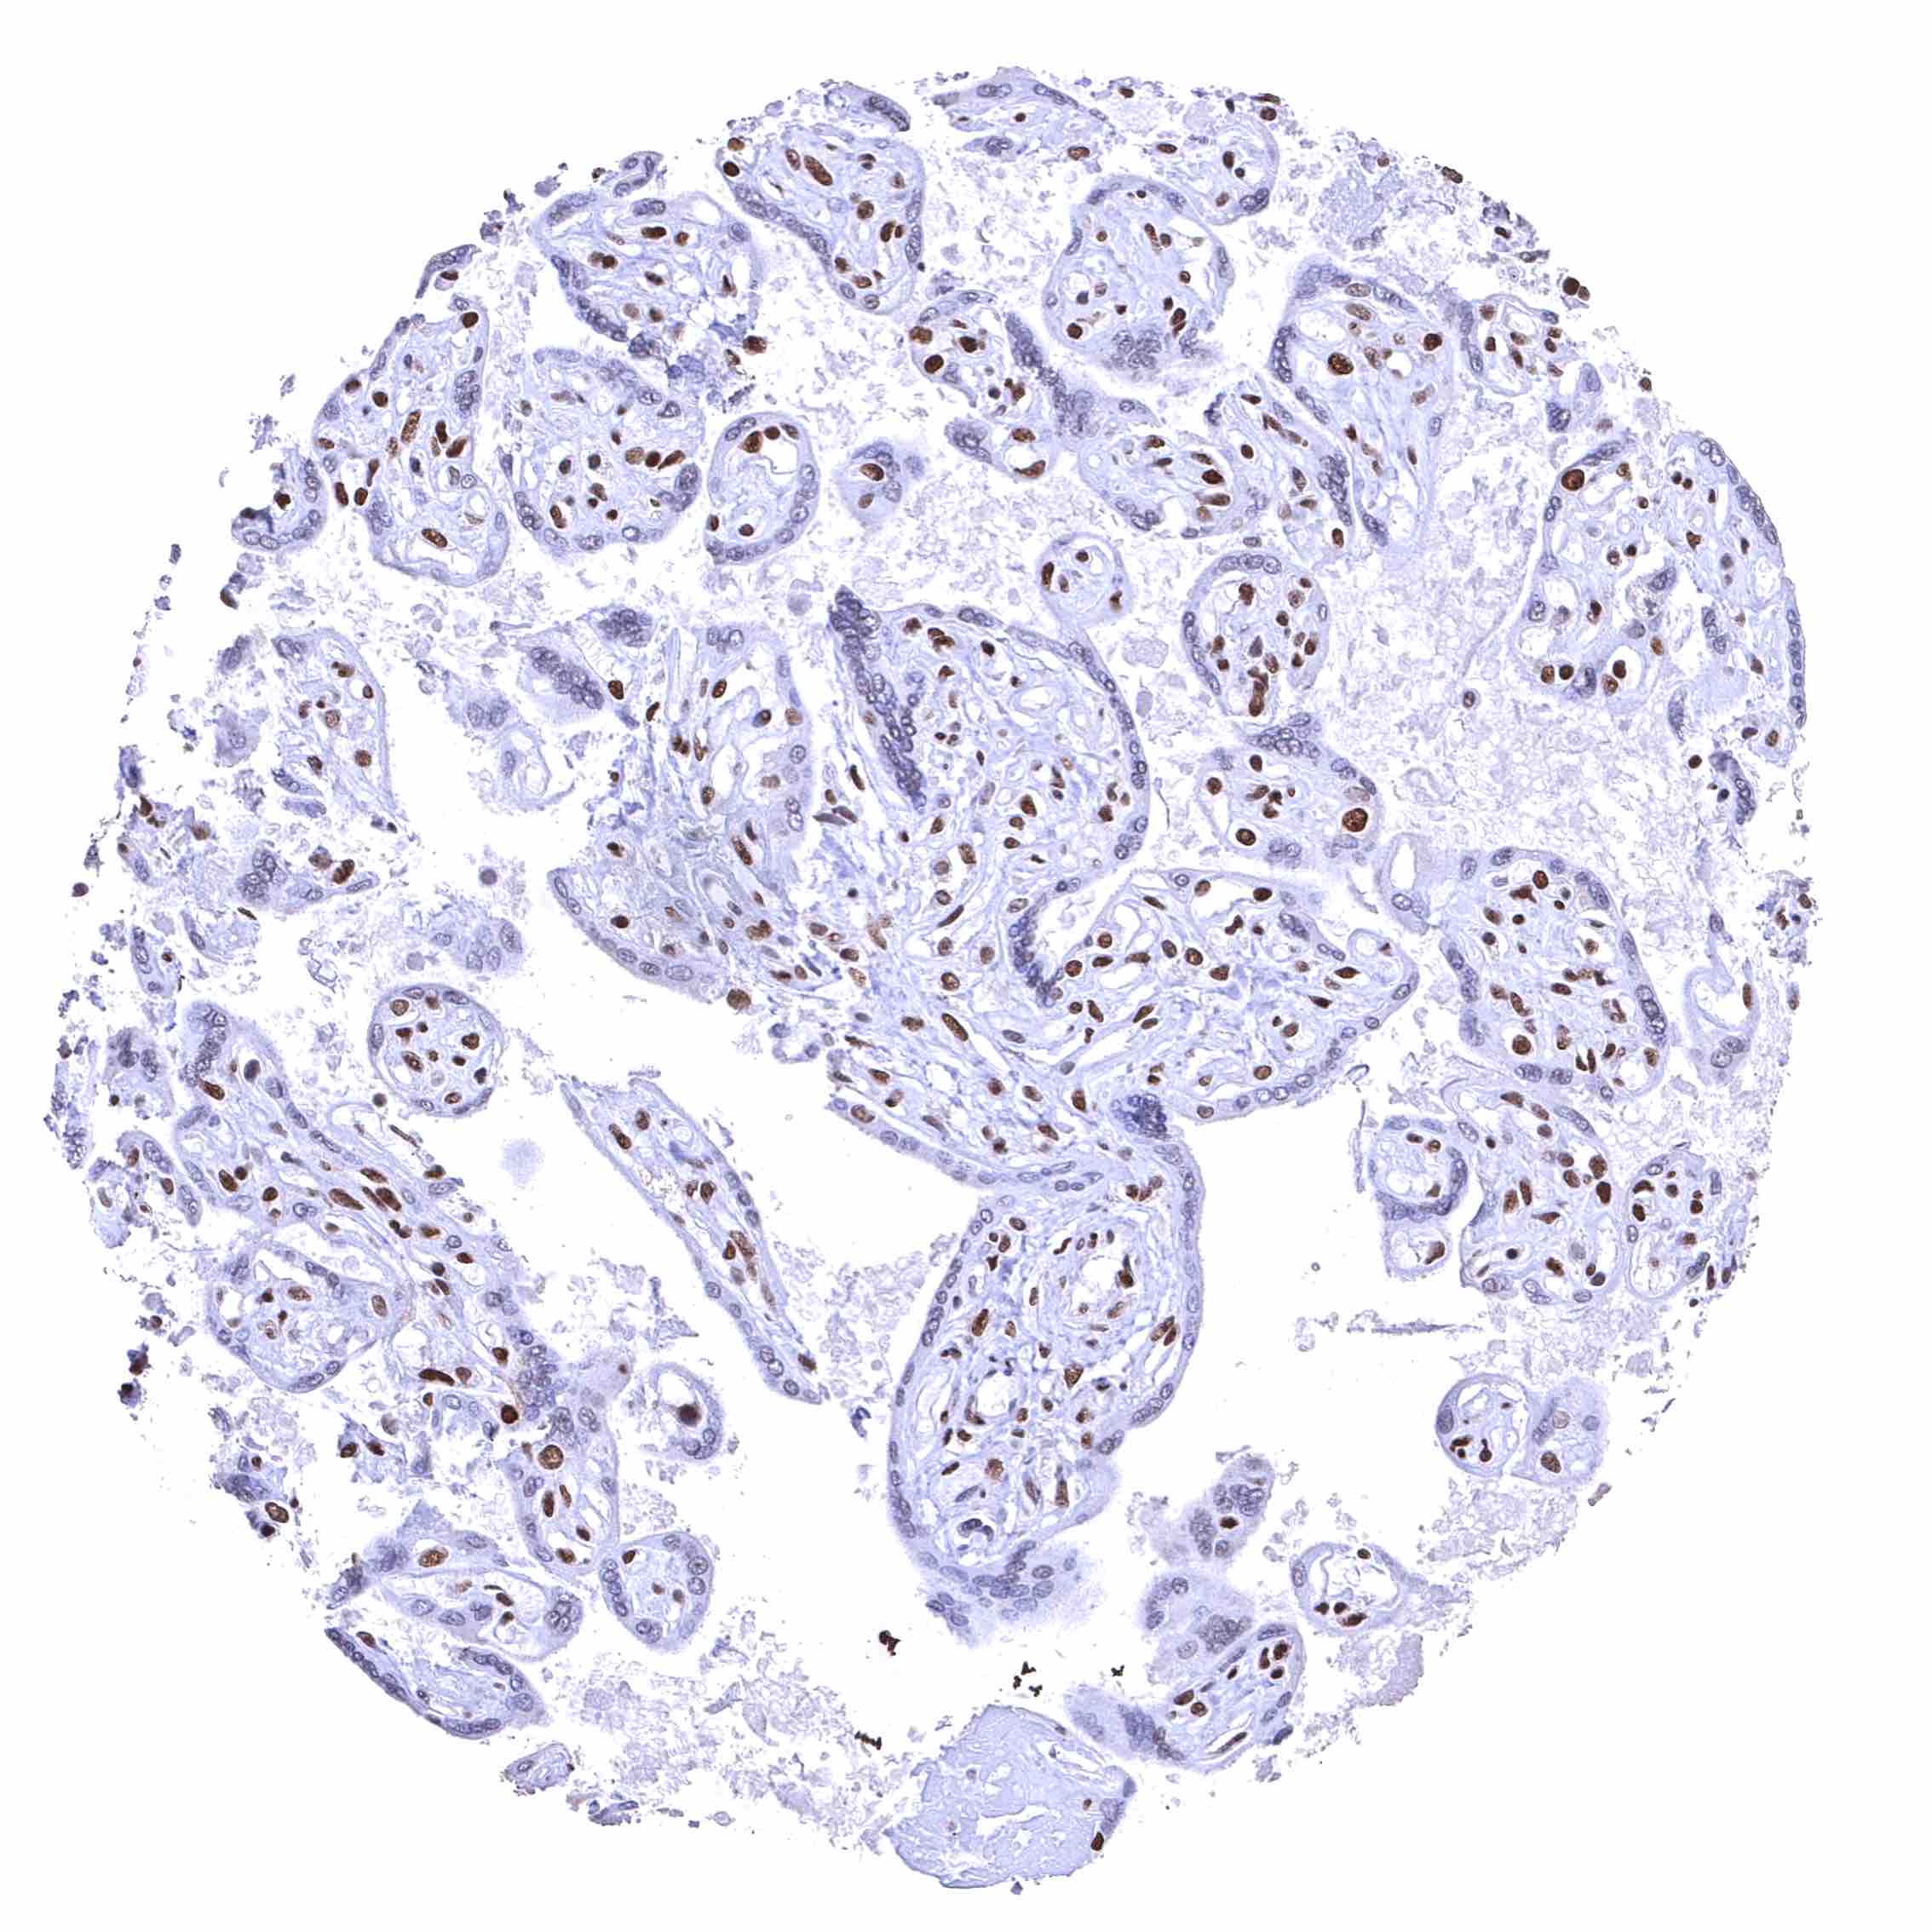

Placenta, mature – BRD4 staining is either absent or massively reduced in the syncytiotrophoblast.